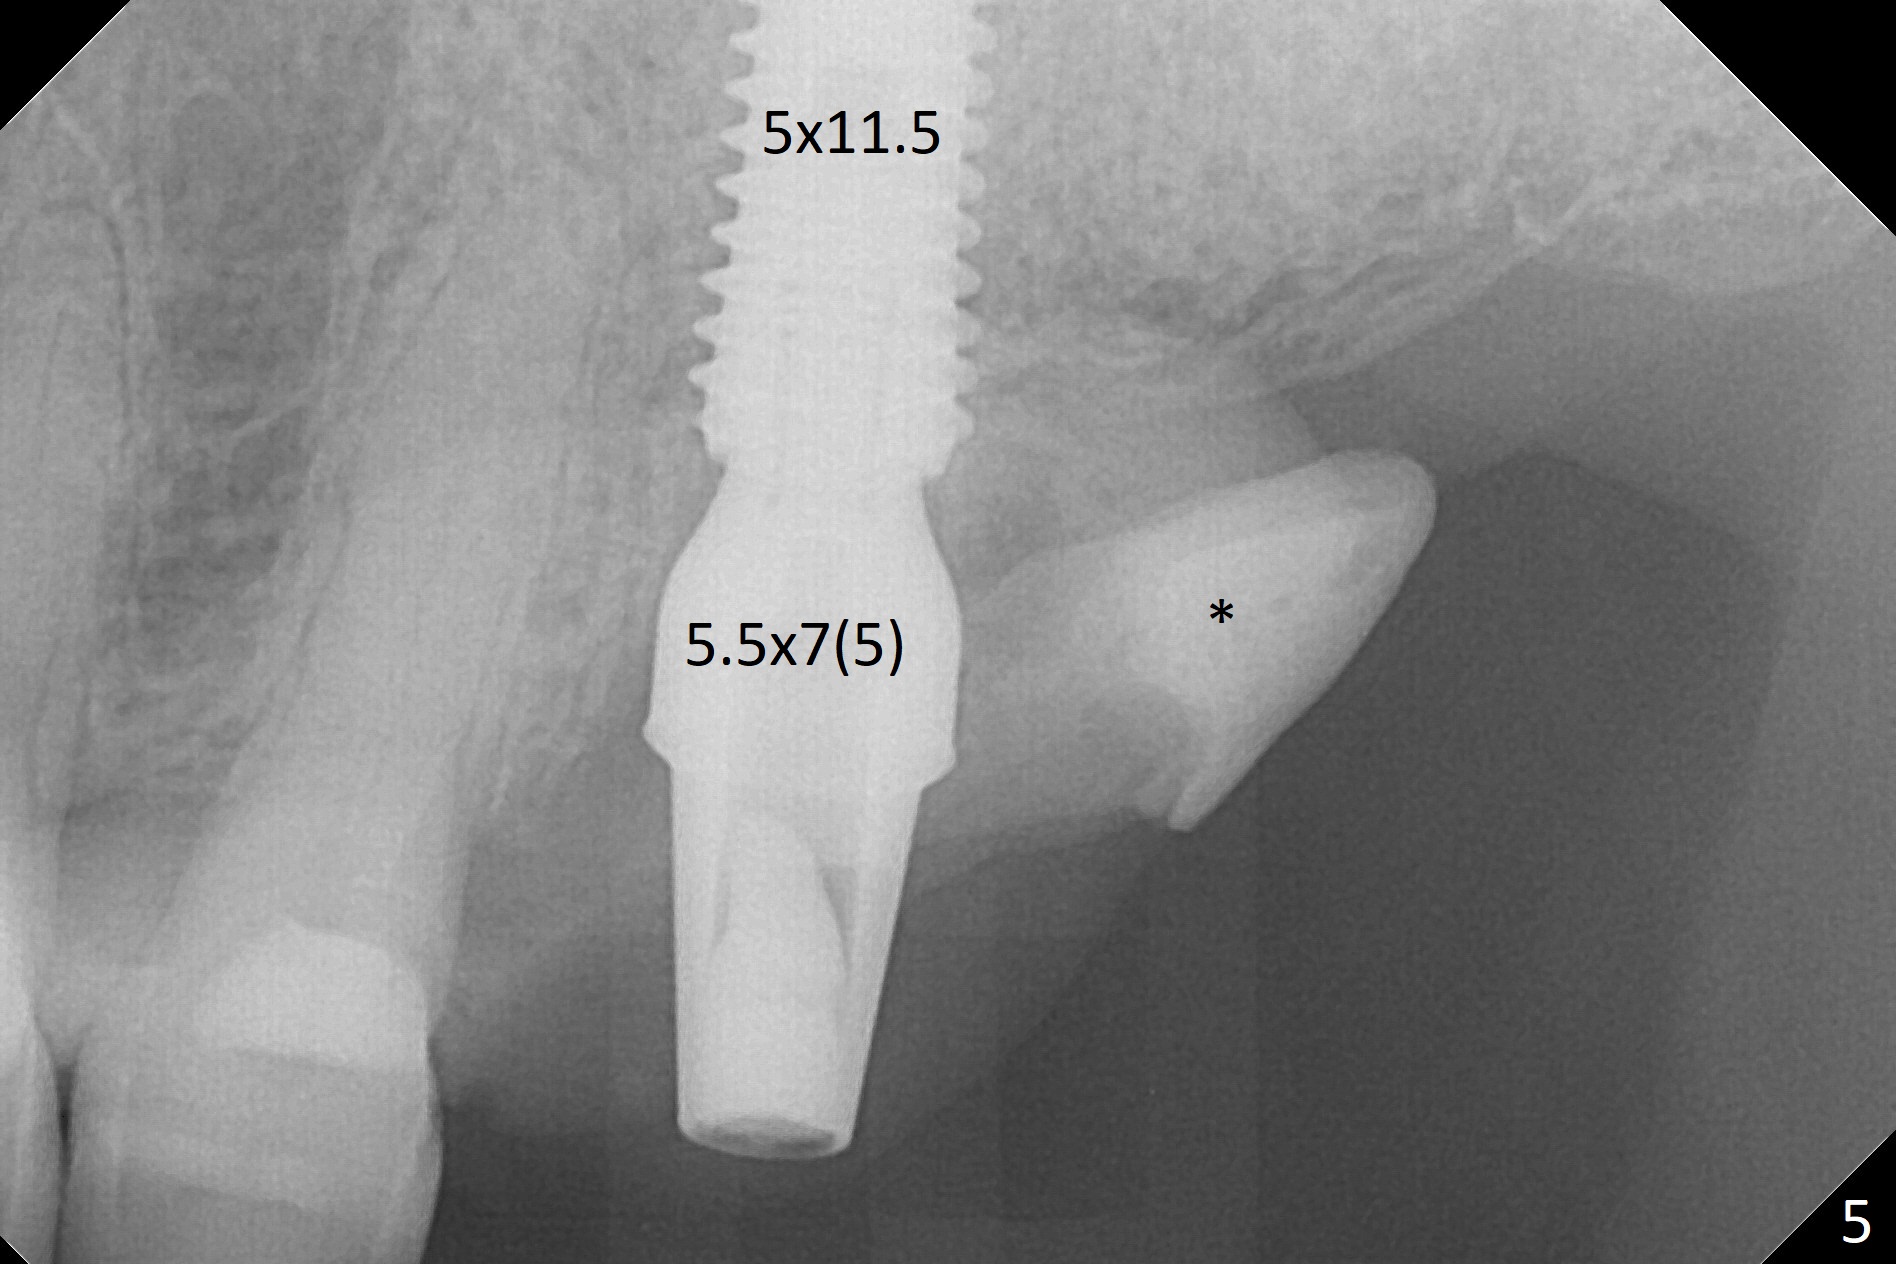

The septum is found to be pointed after extraction of the tooth #14 (Fig.1 *). The septum is flattened with Rongeur (Fig.2 *) prior to osteotomy. Because of interference of the mesial bone (Fig.3 *), osteotomy does not reach the depth with use of stopper. Without the latter, a 5x11.5 mm implant barely penetrates the sinus floor (Fig.4 (no postop nasal hemorrhage)). Also due to the mesial bone interference, a 6.5 mm abutment is not seated. Finally a 5.5x7(5) mm abutment is placed for an immediate provisional. Periodontal dressing is applied to cover the buccal repaired gingiva (Fig.5 *). There is minimal thread exposure after removal of the provisional nearly 2 months postop (Fig.6). The provisional does not return for easy self cleansing. In fact this is not an easy task, because of the posterior position (Fig.8 (after Piezo scaling)). The distal implant remains exposed; the abutment is removed and a healing screw is placed (Fig.9). The implant should have been subcrestal distally (Fig.7 <, nearly 3 months postop). One month later, the implant seems to be buried (Fig.10). The straight abutment is changed to an angled one (4.5 x15 degree A (5) mm) before impression retake (Fig.11,12 (<, dashed line: access hole)). The implant should have been placed more mesial (Fig.13). Surgical guide is needed. There is no implant exposure clinically or in CBCT sections 1 year 2 months post cementaton (Fig.14), although 3 D image suggests missing distopalatal plate (Fig.15).